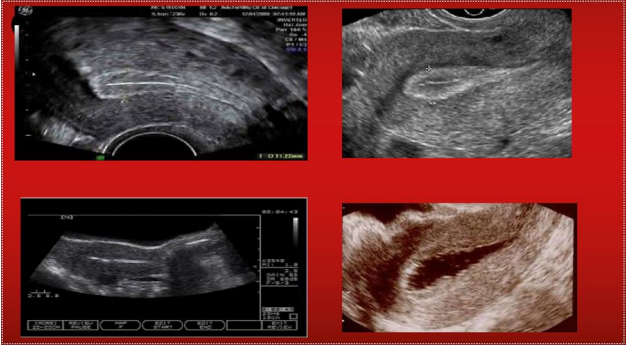

Fig 1: Endomertium Lining in IVF

Figure 1